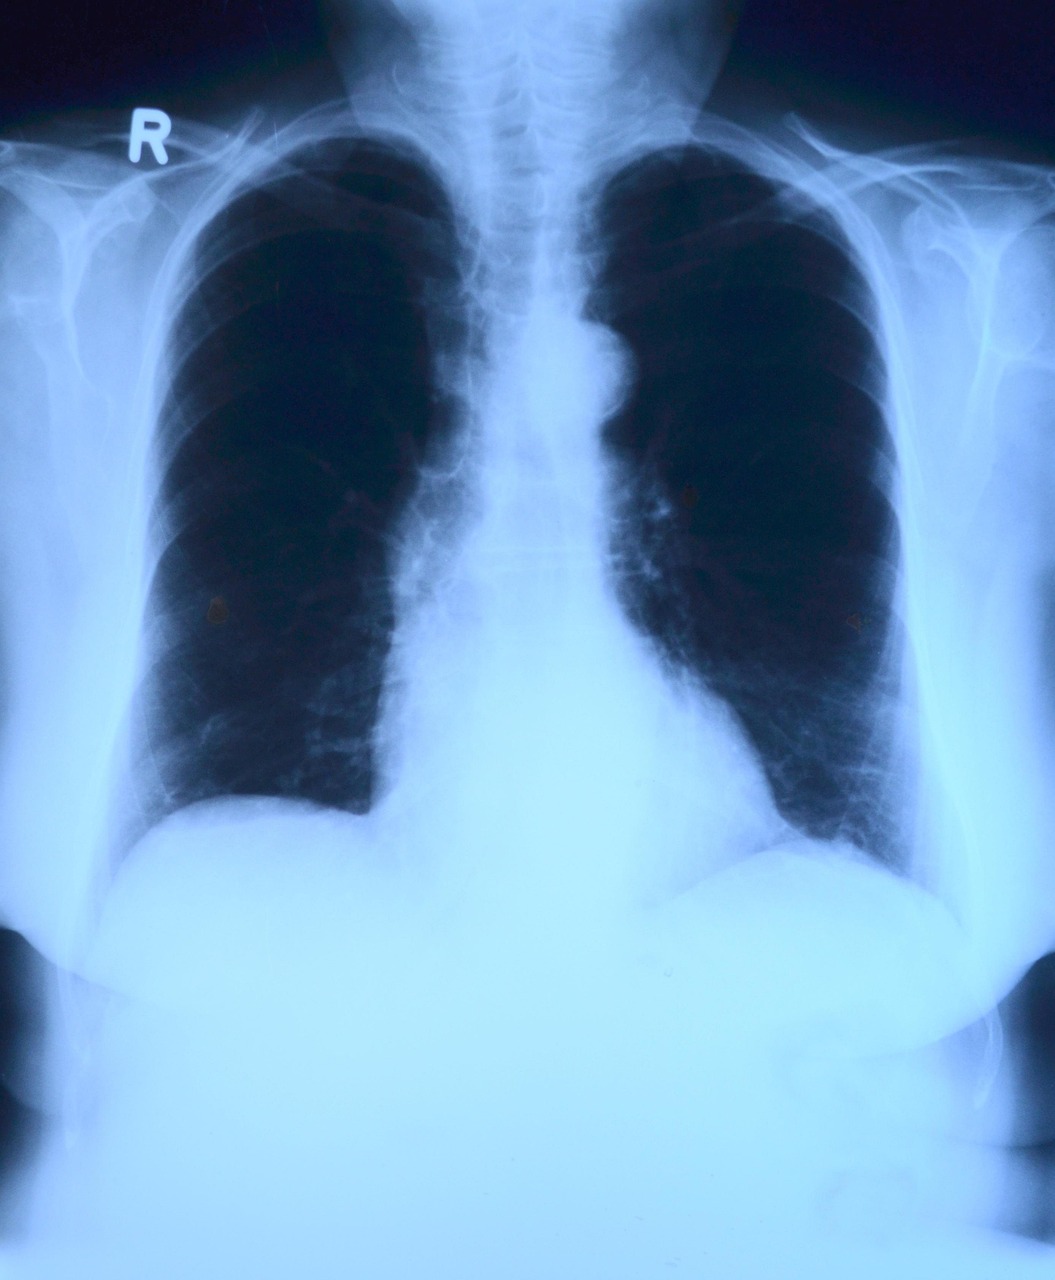

니코틴과 타르, 그리고 매일 쌓이는 숨겨진 폐 손상 이야기

담배 한 개비 피울 때마다, 사실 우리 폐 안에서는 아주 복잡하고 위험한 변화들이 일어나고 있습니다. 그저 '몸에 나쁘다' 정도로만 알고 있던 흡연의 영향은 생각보다 훨씬 구체적이고, 심각하죠. 폐 깊숙이 스며드는 니코틴과 타르, 눈에 보이지 않게 쌓이는 손상, 숨이 차고 기침이 늘어나는 불편함까지… 단순 경고 문구로는 느끼기 어려운 진짜 피해를 오늘 풀어보겠습니다.

이번 글에서는 흡연이 폐를 어떻게 망가뜨리는지, 의학적 근거와 함께 5가지 주요 메커니즘을 소개하려고 합니다. 니코틴과 타르가 폐 세포를 어떻게 손상시키는지, 만성폐쇄성폐질환(COPD)와 폐암 위험이 왜 올라가는지, 폐의 자정 능력이 왜 떨어지는지, 그리고 산소 공급까지 어떻게 방해받는지 차근차근 짚어볼게요. 읽다 보면 '이제 정말 끊어야겠다'는 생각이 절로 들 수도 있습니다.

니코틴은 단순히 중독을 유발하는 성분으로만 알려져 있지만, 혈관을 수축시켜 폐포에 전달되는 산소량을 줄입니다. 타르는 더 직접적이죠. 끈적한 타르 성분이 폐포와 기관지 벽에 달라붙어 염증을 유발하고, 점막 기능을 떨어뜨립니다. 시간이 지날수록 폐가 딱딱해지고, 폐활량이 감소하게 됩니다.

흡연은 COPD의 가장 큰 원인입니다. 담배 연기 속 유해 물질이 기관지 벽을 두껍게 만들고, 점액 분비를 늘려 기도가 좁아집니다. 결국 숨쉬기가 점점 힘들어지고, 계단 몇 개만 올라가도 숨이 차는 상태가 됩니다.

담배 연기에는 70종 이상의 발암 물질이 들어 있습니다. 이 물질들이 폐세포의 DNA를 손상시키고, 변이 세포가 생겨나면서 암으로 진행될 수 있습니다. 흡연 기간과 양이 많을수록 위험은 기하급수적으로 높아집니다.

흡연이 폐에 미치는 영향은 생각보다 훨씬 빠르고 깊게 진행됩니다. 니코틴과 타르가 만드는 구조적 손상, COPD와 폐암 위험, 폐의 자정 능력 저하, 산소 공급 차단까지… 이 모든 과정은 담배를 피우는 순간부터 시작됩니다. 하지만 좋은 소식은, 금연을 결심하는 순간 폐는 회복을 시작한다는 사실입니다. 지금이 바로 그 결심을 실천할 최적의 시점입니다. 여러분은 오늘, 폐를 위한 선택을 하실 건가요?